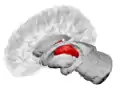

The thalamus is a paired structure of gray matter located in the forebrain which is superior to the midbrain, near the center of the brain, with nerve fibers projecting out to the cerebral cortex in all directions. The medial surface of the thalamus constitutes the upper part of the lateral wall of the third ventricle, and is connected to the corresponding surface of the opposite thalamus by a flattened gray band, the interthalamic adhesion. The lateral part of the thalamus is the phylogenetically newest part of the thalamus (neothalamus), and includes the lateral nuclei, the pulvinar and the medial and lateral geniculate nuclei.[6][7] There are areas of white matter in the thalamus including the stratum zonale that covers the dorsal surface, and the external and internal medullary laminae. The external lamina covers the lateral surface and the internal lamina divides the nuclei into anterior, medial and lateral groups.[8]

Thalamic nuclei

The thalamus comprises a system of lamellae (made up of myelinated fibers) separating different thalamic subparts. Other areas are defined by distinct clusters of neurons, such as the periventricular nucleus, the intralaminar elements, the "nucleus limitans", and others.[11] These latter structures, different in structure from the major part of the thalamus, have been grouped together into the allothalamus as opposed to the isothalamus.[12] This distinction simplifies the global description of the thalamus.